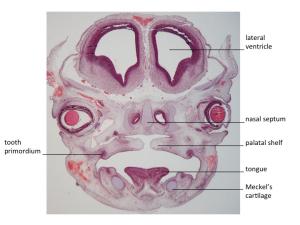

Stage 20

CfS 20

d35-38